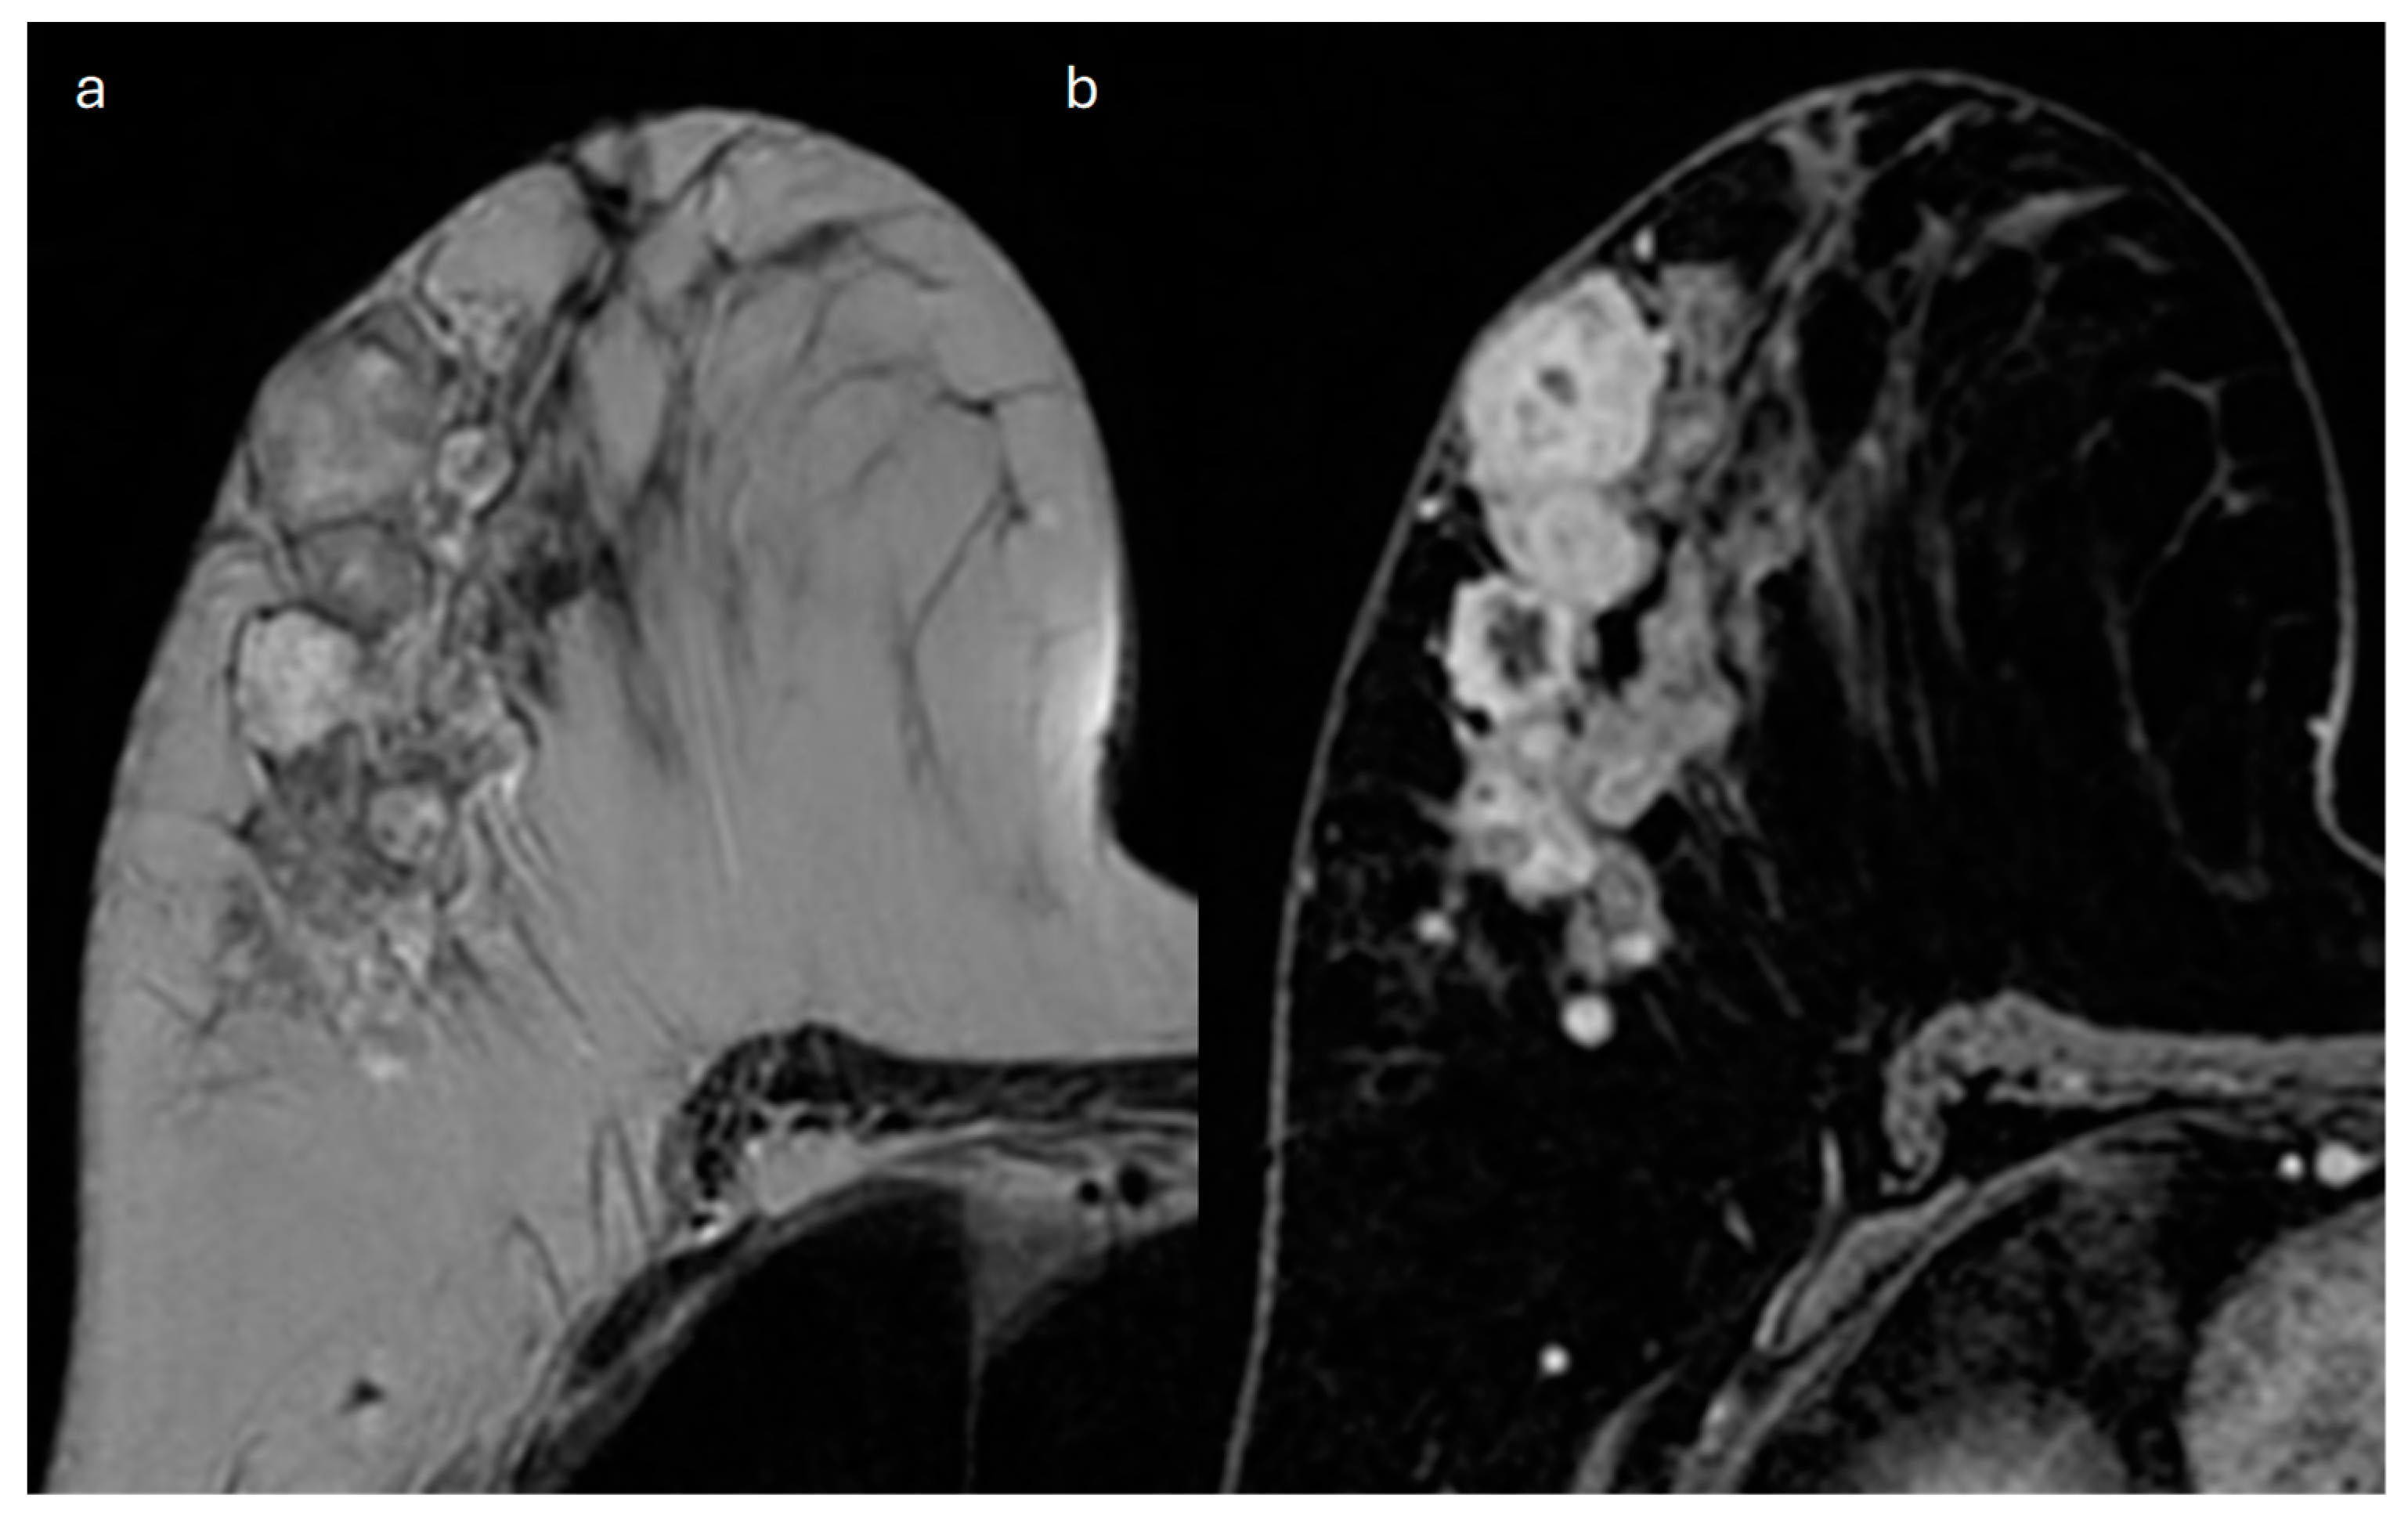

10. Metaplastic